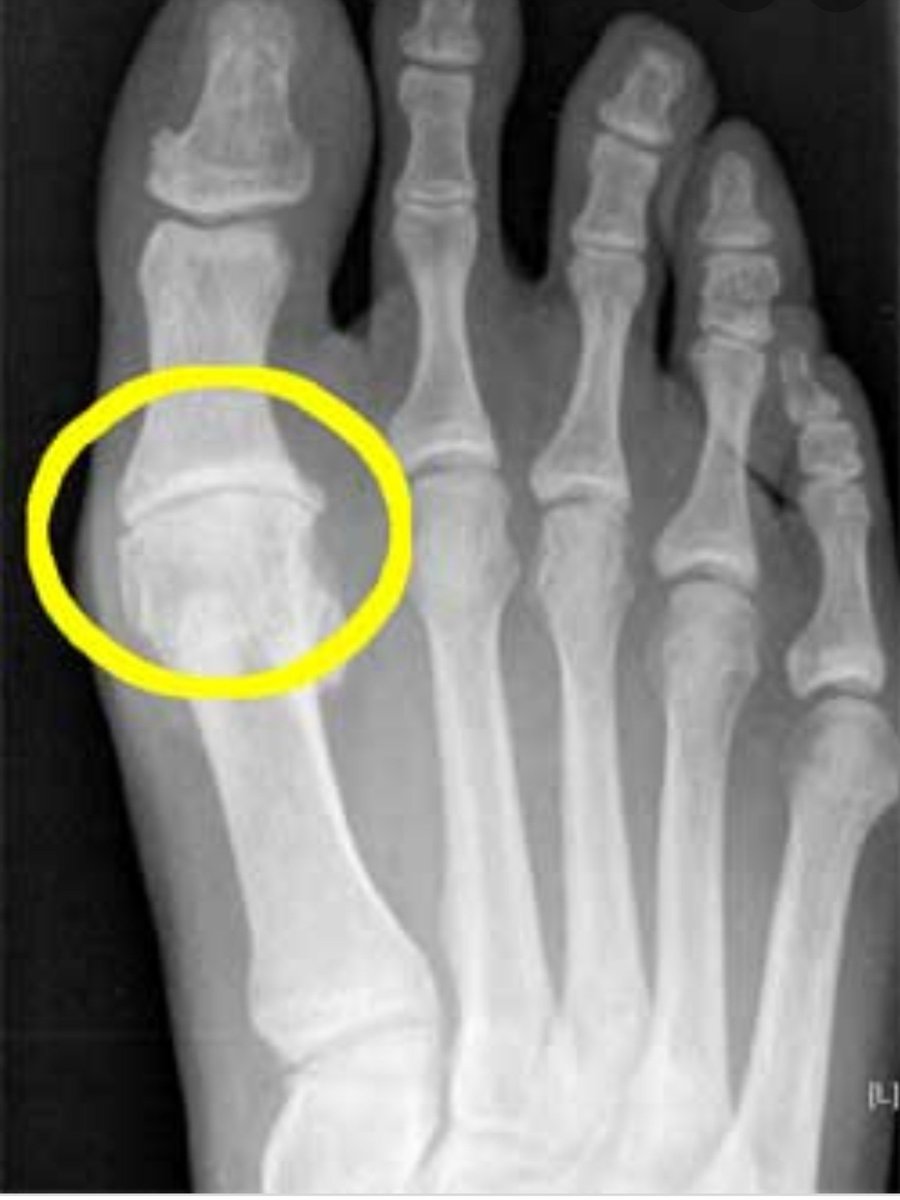

الاشعة:

-خشونة و تضيق بالمفصل

-وجود زوائد عظمية في الجزء الأعلى من المفصل

-وجود انحراف في الإصبع الكبير